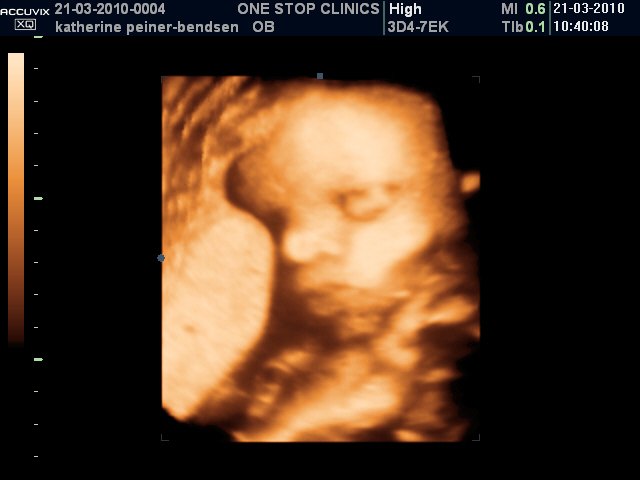

Scanningsbilleder af Alexander taget i uge 31.

Han puttede sig godt ind mod moderkagen med sin højere side af ansigtet, så vi fik desværre aldrig et fuldt profilbillede af den lille gut  Men tilgengæld oplevede vi, at han åbnede sine øjne en del gange og blinkede til os

Vedhæftede fotos (klik for at se i fuld størrelse)